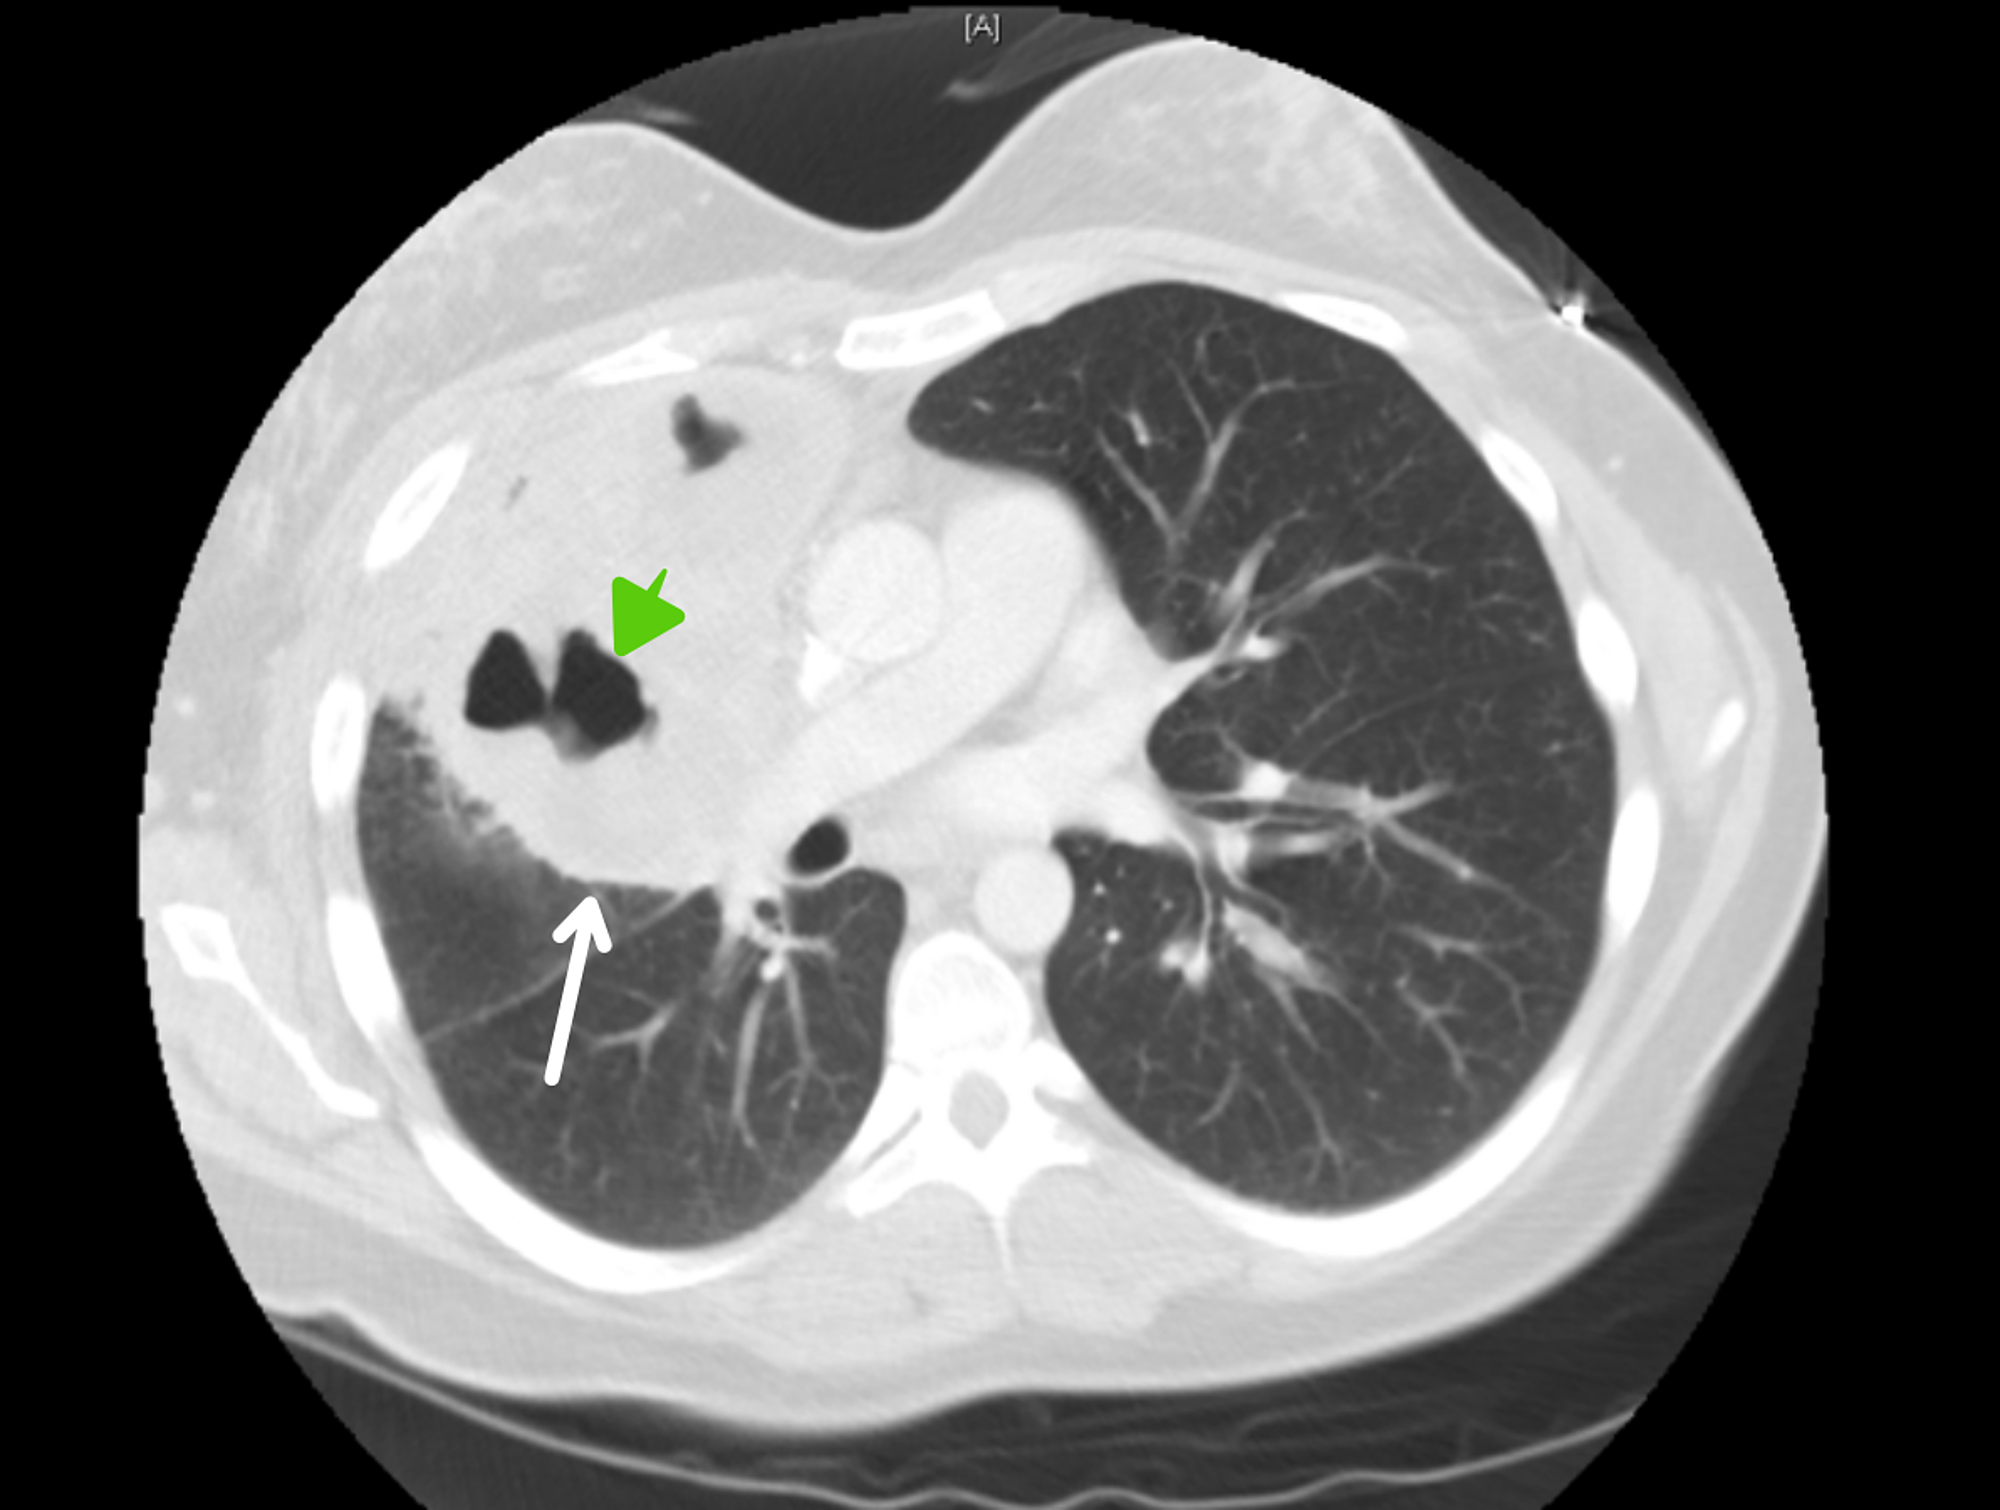

From ctisus.com

Lymphoma with Mediastinal, Lung Parenchymal and Renal Involvement Can A Chest X Ray Diagnose Lymphoma The etiology is unknown but potential. Lymphoma diagnosis often begins with an exam that checks for swollen lymph nodes in the neck, underarm and groin. The best way to diagnose lymphoma is to perform a biopsy of a lymph. The amount of radiation exposure during a ct scan varies depending on the area scanned. To look for possible signs of. Can A Chest X Ray Diagnose Lymphoma.